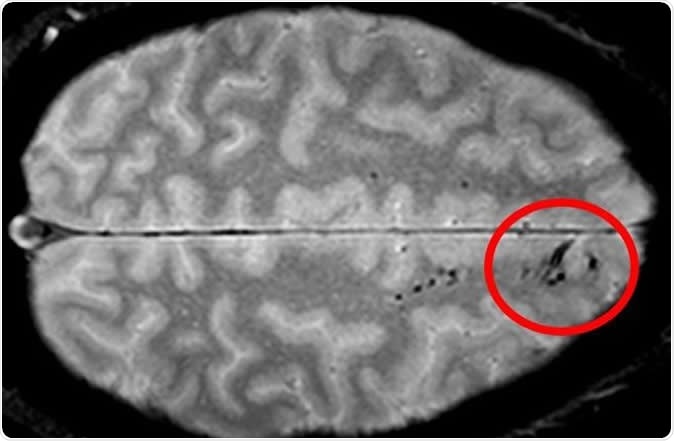

Traumatic microbleeds appear as dark lesions on MRI scans and suggest damage to brain blood vessels after head injury. Image Credit: Latour Lab/NINDS.

Microbleeds are small areas of hemorrhage that are not detectable by CT scanning but are picked up by MRI as tiny dark patches. They are caused by blood vessel injury, and may be found after apparently even minor degrees of head injury. The problems caused by this type of damage to blood vessels is not quite clear but since any injury to brain cells can be potentially wide in its impact, the researchers feel that microbleeds need to be studied in greater depth.

The appearance of the microbleeds was also variable – some were linear, while others were punctate (like small dots), and most patients showed both types. The area of the brain most likely to show microbleeds was the frontal region of both hemispheres.